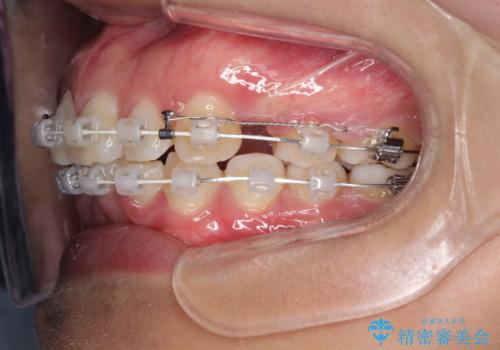

- 矯正装置

- 審美装置

上の歯の前から4番目の歯を2本抜歯して、そのスペースに前歯を移動させて、前歯を引っ込める計画としました。

抜歯をすることでしっかり前歯を後方に移動させて、引っ込めることができました。